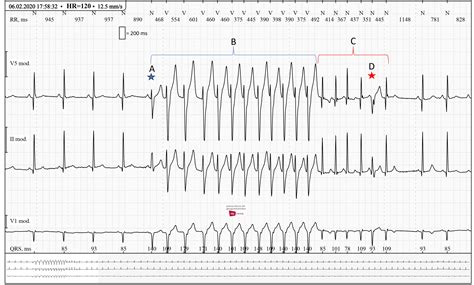

Diagnosing sinus bradycardia involves a thorough medical evaluation, including a detailed medical history, physical examination, and diagnostic tests. The primary diagnostic tool is the electrocardiogram (ECG), which records the electrical activity of the heart. An ECG can confirm the presence of sinus bradycardia by showing a regular rhythm with a heart rate below 60 bpm. Additional tests may include: